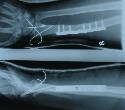

Pic Title: Fixed

Pic Description: Many thanks to the orthopoedic surgeons at East Surrey Hospital.